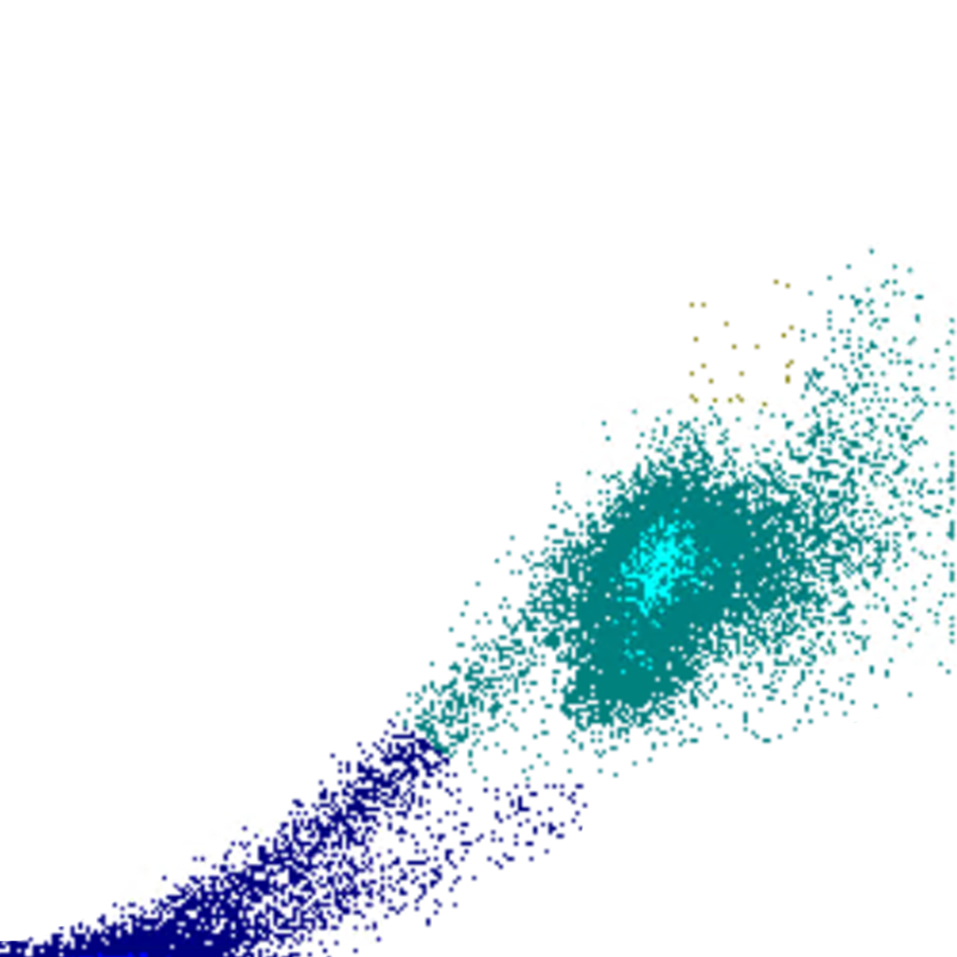

Selon les paramètres représentés l’un par rapport à l’autre, la combinaison de ces signaux détermine la position de chaque cellule sur le diagramme de dispersion. Cela génère des clusters caractéristiques pour les populations cellulaires normales et des motifs reconnaissables en cas d’anomalies.

Densité

La densité des points dans un diagramme de dispersion reflète le nombre de cellules présentant des caractéristiques physiques et de fluorescence similaires. Le diagramme indique ainsi non seulement la présence de populations cellulaires, mais aussi leur taille relative et leur homogénéité.

• Une forte densité de points indique une population cellulaire importante et relativement homogène

• Des motifs diffus ou dispersés peuvent suggérer une hétérogénéité, une activation ou la présence de cellules anormales

• Des déplacements, un élargissement ou un chevauchement entre populations constituent souvent des signes précoces de morphologie anormale ou de cellules rares